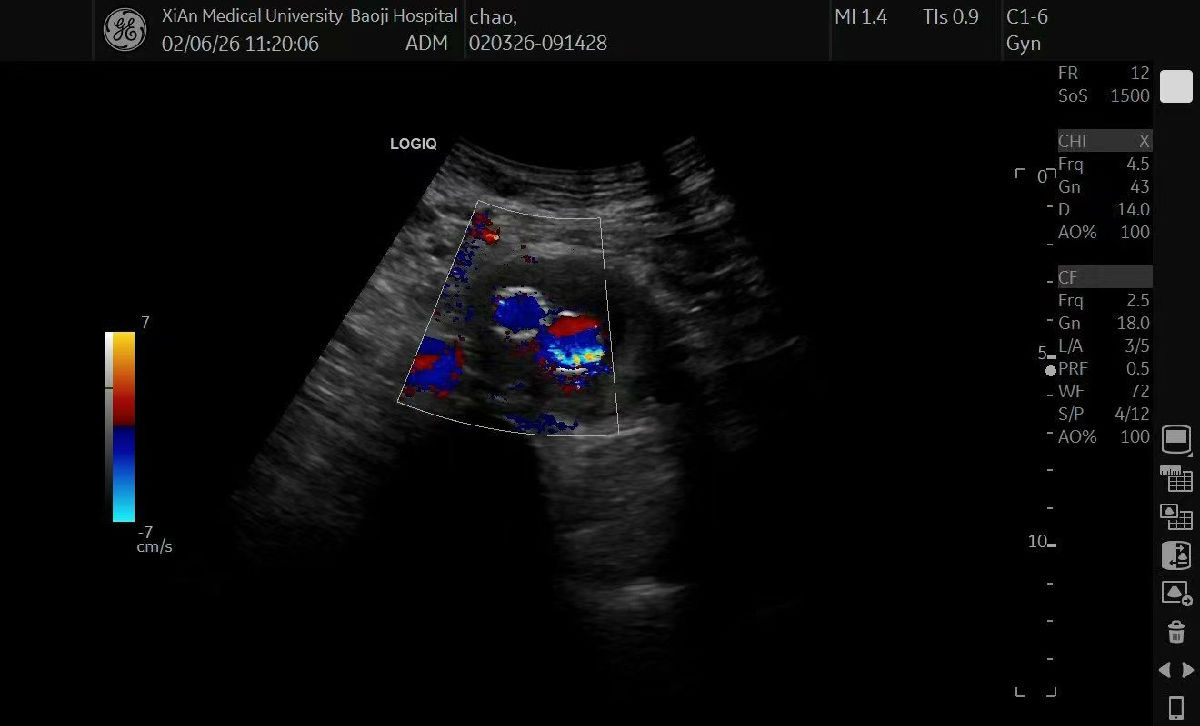

华西医院心脏大血管外科团队针对患者病情特点,精心设计了“人字形支架植入术”,手术中,将支架从腹主动脉脐部水平植入,延伸至双侧髂总动脉,实现对病变血管的全程覆盖与有效支撑,成功封闭夹层破口,高难度完成手术,为患者解除生命威胁。

此次患者返回我院超声医学科复查,超声显示支架位置精准、血流通畅,恢复情况理想。“当时真的非常害怕,多亏咱超声医学科的医生精准细致的检查,华西医院的专家又妙手解难,我才重获健康!”患者紧紧握住科室医护人员的手,激动地表示感谢。